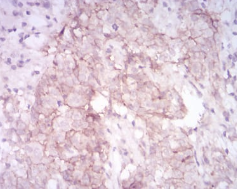

MMP14 Mouse Monoclonal antibody[61D1]

IHC    1/200 - 1/1000